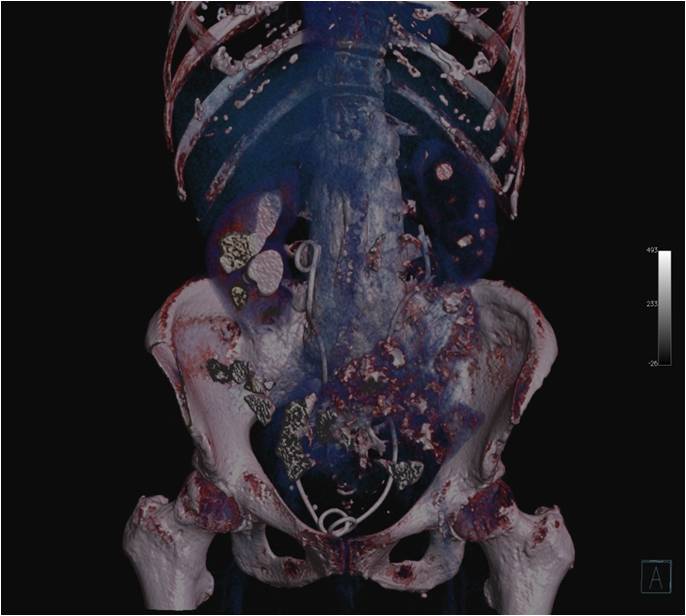

Idiopathic retroperitoneal fibrosis, or Ormond’s disease, is a rare syndrome which is in essence the deposition of pathological fibrous tissue in the retroperitoneal space. In most cases, it is initially asymptomatic, but as the disease progresses, clinical symptoms develop. The main complaint are abdominal pain and symptoms resulting from the involvement of ureters, arterial and venous vessels. Diagnosis is based on computed tomography or magnetic resonance imaging, demonstrating a fibrotic tissue mass accumulated in the retroperitoneal space. Due to the typically late presentation of clinical symptoms, a diagnosis is difficult and is often made after complications occur. In our article, we present the case of a 71-year-old patient in whom coexisting ankylosing spondylitis and retroperitoneal fibrosis were diagnosed 15 years after non-specific abdominal pain occurred.